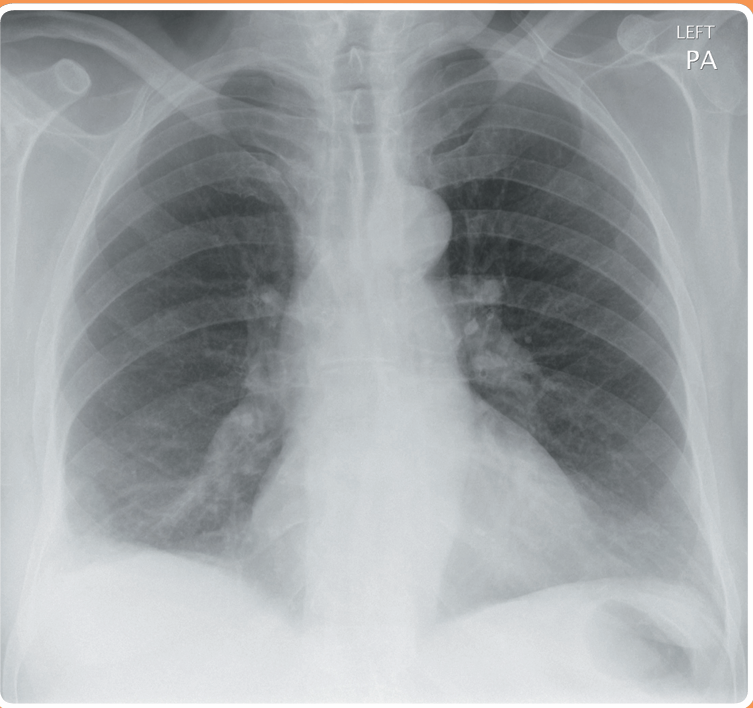

Una mujer de 71 años se presenta a la sala de emergencias con dolor torácico y dificultad para respirar. Hace 2 semanas se sometió a una reemplazo total de cadera izquierdo. No es fumadora. En el examen físico, presenta saturaciones del 91% en aire y no tiene fiebre. Los campos pulmonares son resonantes en toda su extensión, con buena entrada de aire bilateralmente. Se solicita una radiografía de tórax para evaluar posible neumonía, colapso, derrame o embolia pulmonar.

La radiografía muestra un pequeño derrame pleural derecho con consolidación asociada menor. Esto podría reflejar una neumonía con un derrame parapneumónico. La otra principal posibilidad diagnóstica, especialmente debido a la cirugía reciente, es una embolia pulmonar con infarto (consolidación) y derrame pleural.

Se debe administrar oxígeno suplementario.

Las pruebas iniciales de laboratorio pueden incluir gases arteriales, hemograma (FBC), análisis de electrolitos y función renal (U/Es), pruebas de función hepática (LFTs), hemocultivos, coagulación y proteína C reactiva (CRP). Los cultivos de esputo también serían útiles. El D-dímero es poco probable que sea útil debido a la cirugía reciente. Se debe considerar una tomografía computarizada con angiografía pulmonar (CT Pulmonary Angiogram).

El tratamiento con antibióticos o heparina de bajo peso molecular se guiará por los resultados de las investigaciones anteriores.